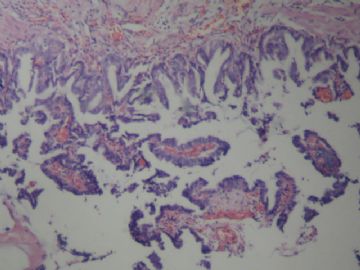

• 胆囊图1

图1

慢性胆囊炎 腺体中度不典型增生

腺癌,像是粘液腺癌,不知在显微镜下粘液是否明显.

腺体重度异型增生(注意有无明确浸润)

在粘膜层,1、2图在粘膜浅肌层。未见明显浸润。

无明显浸润,诊断癌证据不足。

考虑慢性胆囊炎,局部腺体中重度不典型增生

诊断癌证据不足。慢性胆囊炎 腺体中度不典型增生

局部见腺体中度不典型增生。标记P53和增殖活性(Ki-67) 。

图1和2够不上浸润,因为这样的腺体似是因炎症而陷入的,类似于腺肌症。

不够癌,不典型增生-中度